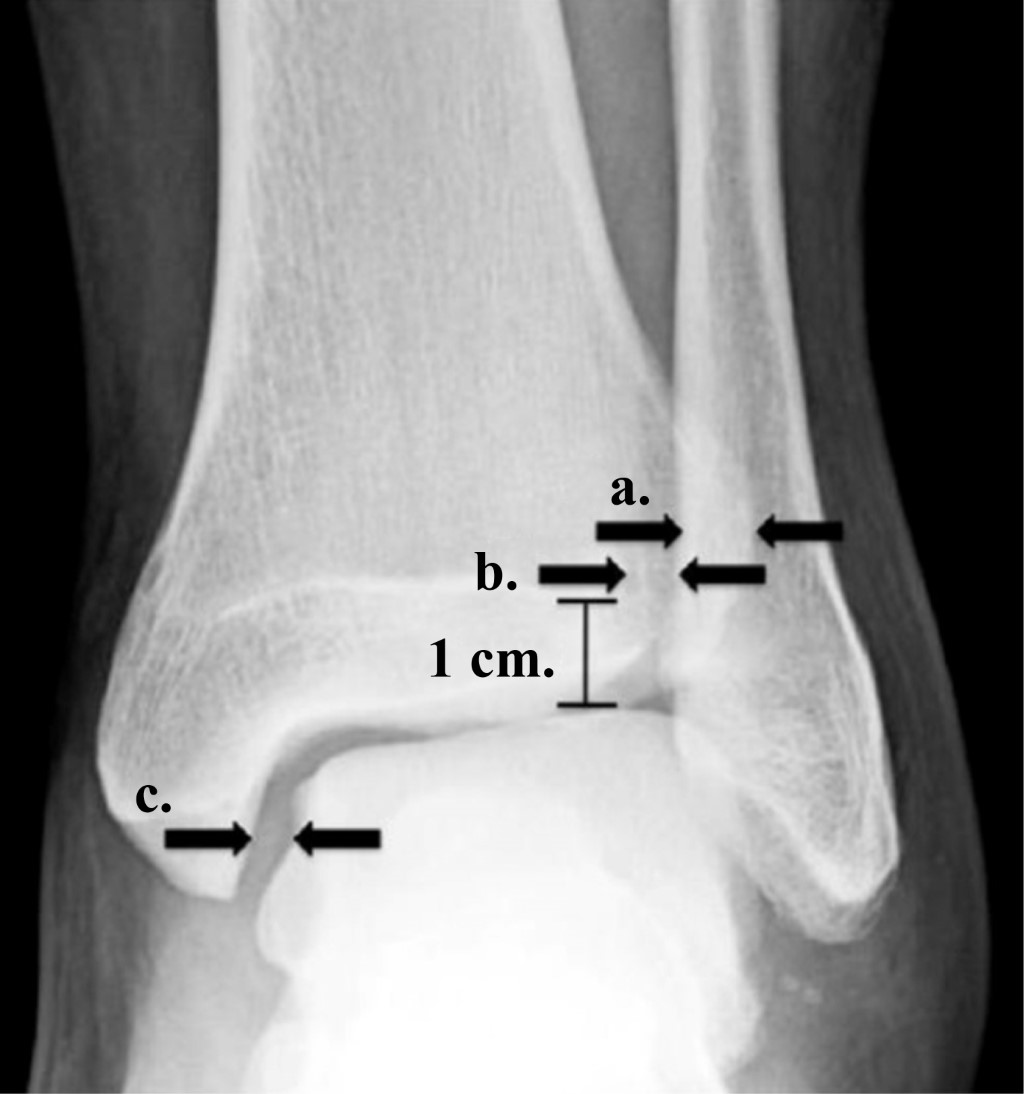

Se realizaron tres mediciones radiográficas, las cuales fueron: el espacio tibioperoneo (ETP), que es la distancia entre el borde medial del peroné y el borde lateral del tubérculo posterior de la tibia; la superposición tibioperonea (STP), que es la distancia entre el borde medial del peroné y el borde lateral del tubérculo anterior de la tibia; y el espacio astrágalo-tibial medial (EATM), que es la distancia entre el borde medial del astrágalo y el borde lateral del maléolo medial (Figura 3).

En la radiografía anteroposterior y en la proyección de la mortaja, existen mediciones que nos ayudan a realizar el diagnóstico de integridad de la sindesmosis tibioperonea distal. Estas son: el espacio tibioperoneo (ETP), que es la distancia que existe entre el borde medial del peroné y el borde lateral del tubérculo posterior de la tibia, cuyo valor normal es < 6 mm; la superposición tibioperonea (STP), que es la distancia que existe entre el borde medial del peroné y el borde lateral del tubérculo anterior de la tibia, cuyo valor normal es > 6 mm; y el espacio astrágalo-tibial medial (EATM), que es la distancia que existe entre el borde medial del astrágalo y el borde lateral del maléolo medial, para el cual se describe un valor normal de 4 mm.11,12,13 Los valores previamente mencionados, descritos por Marion Harper, concuerdan con los resultados registrados en este estudio.